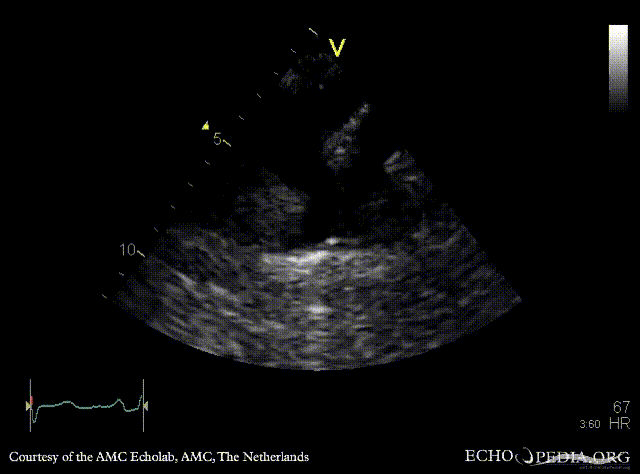

Coarctatio aortae

Courtesy of: AMC Echolab, AMC, The Netherlands

E00361.gif E00362.gif

Suprasternal view Suprasternal view: Collor Doppler, high velocity flow in descending aorta